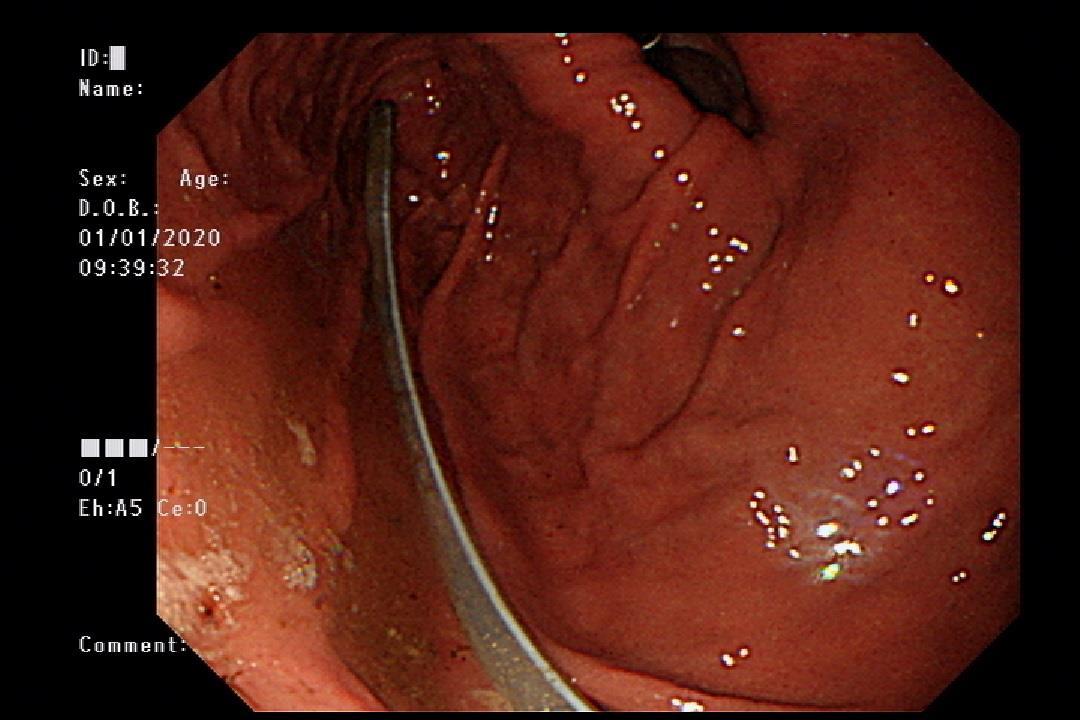

Figure 2: Abroken NG tube is noted in the stomach via endoscope.

Endoscope was performed at ER with the following findings

Esophagus: perifocal hyperemia with small mucosal breaks <5mm in EG junction.

Upward displacement of EG junction over diaphragmatic-esophageal hiatus.

Stomach: chronic hyperemia noted with erosions in antrum. Rapid Hp urease test was done at antrum.Abroken NG tube about 20 cm was noted, removed with a snare catheter.

Duodenum: some small shallow ulcers in bulb. Negative to 2nd portion.